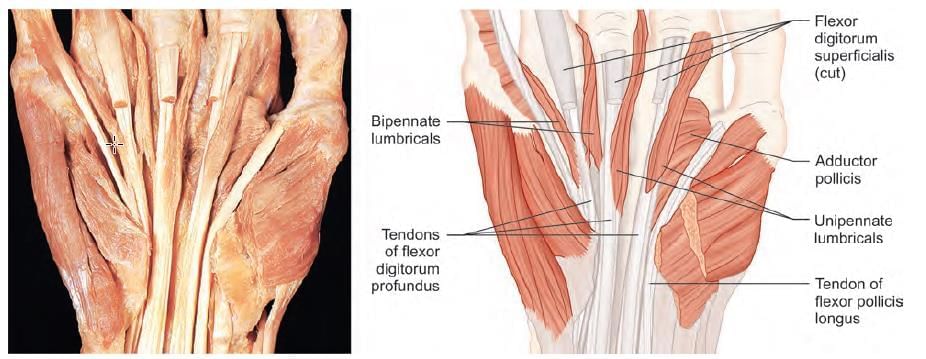

Mention the nerve supply of the marked muscle: (INI-CET May 2022)